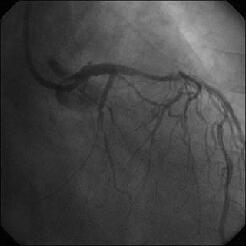

�Ǘ��72�Ώ����Brisk factor��HT, HL, DM�ł��B

��2�T�ԑO�̔��ǂƎv����Recent MI�ł��BLAD#7: total��Tristar3.0�~18?�����

�܂����B

����LCx ostium: 75%�ł��B������PCI���悤�Ǝv���̂ł����A�ǂ̂悤��strategy

���l������ł��傤���H

���Ȃ݂ɓ��@�ł�DCA�g�p�o���҂͂��܂���B

DCA�ł���l��A��Ă���A�Ƃ����I�������܂߂Č䏕��������K���ł��B